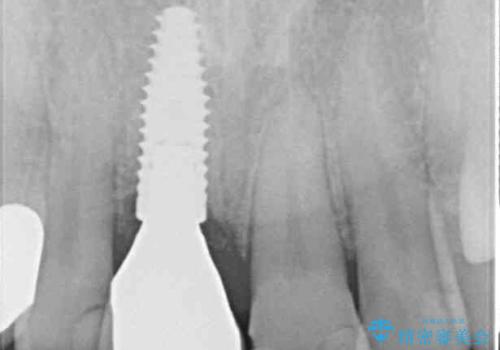

折れてしまった前歯 インプラントによる補綴治療

- 前歯の被せものが脱離したとのことで来院された患者様です。

診察の結果、前歯が縦に破折しており、抜歯が必要と診断されました。

補綴治療としては、インプラントあるいはブリッジの2つがありますが、患者様と相談した結果、インプラントによる補綴治療を選択することとなりました。